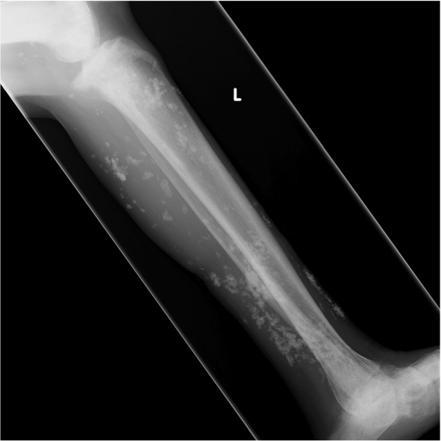

soft tissue calcs, specifically intramuscular. Weakness

polymyositis, dermatomyositis

Soft tissue calcs (most commonly intramuscular)

Polymyositis and dermatomyositis

dermatomyositis